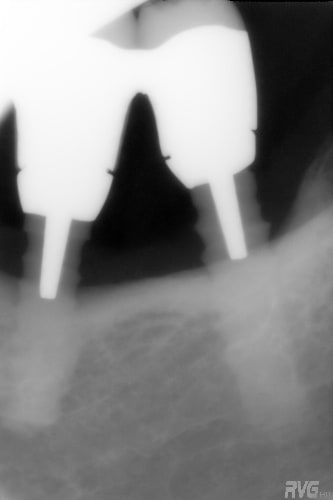

pour le débat, voici ce que j'ai posé en 1990, 1 TBR vissé + 2 zircones vissés de Sandhaus, et voici le résultat 17 ans plus tard. comme le mélange des genres va interpeller, j'explique. il s'agit là de la 2ème pose d'implant de ma carrière débutante, alors que je faisais le DU de la Salpétrière. c'était à l'époque où l'on débatait sur le risque de solidariser un implant à une dent. j'ai finalement préféré ne pas solidariser mes 2 implants 36-37 à la 34 et j'ai donc rajouté un implant en 35 par la suite; entre temps, j'avais abandonné les implants en zircone car la technique chirurgicale proposée avec ne me plaisait pas et que celle proposée pour les implants en titane me convenait davantage. il s'agissait déjà pour Sandhaus de poser les implants sans faire de lambeau et pour le débutant que j'étais, je trouvais ça trop délicat; j'ai donc terminé le cas avec un TBR en technique Branemark plus sécurisante.

suite doc